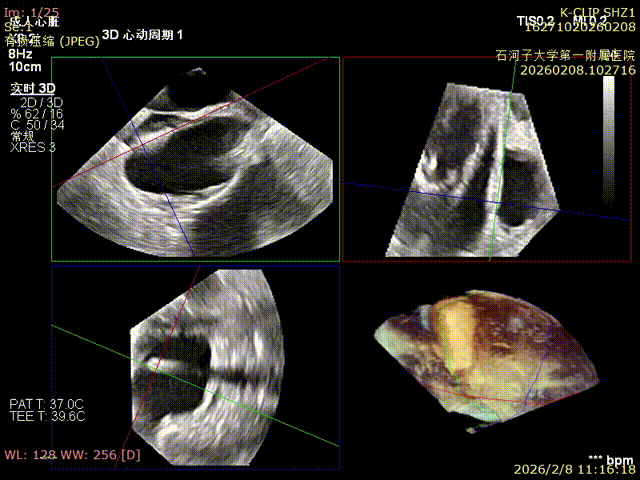

Preoperative anteroseptal regurgitation

Preoperative 3D view of regurgitation

Preoperative TTE: 4-chamber view regurgitation